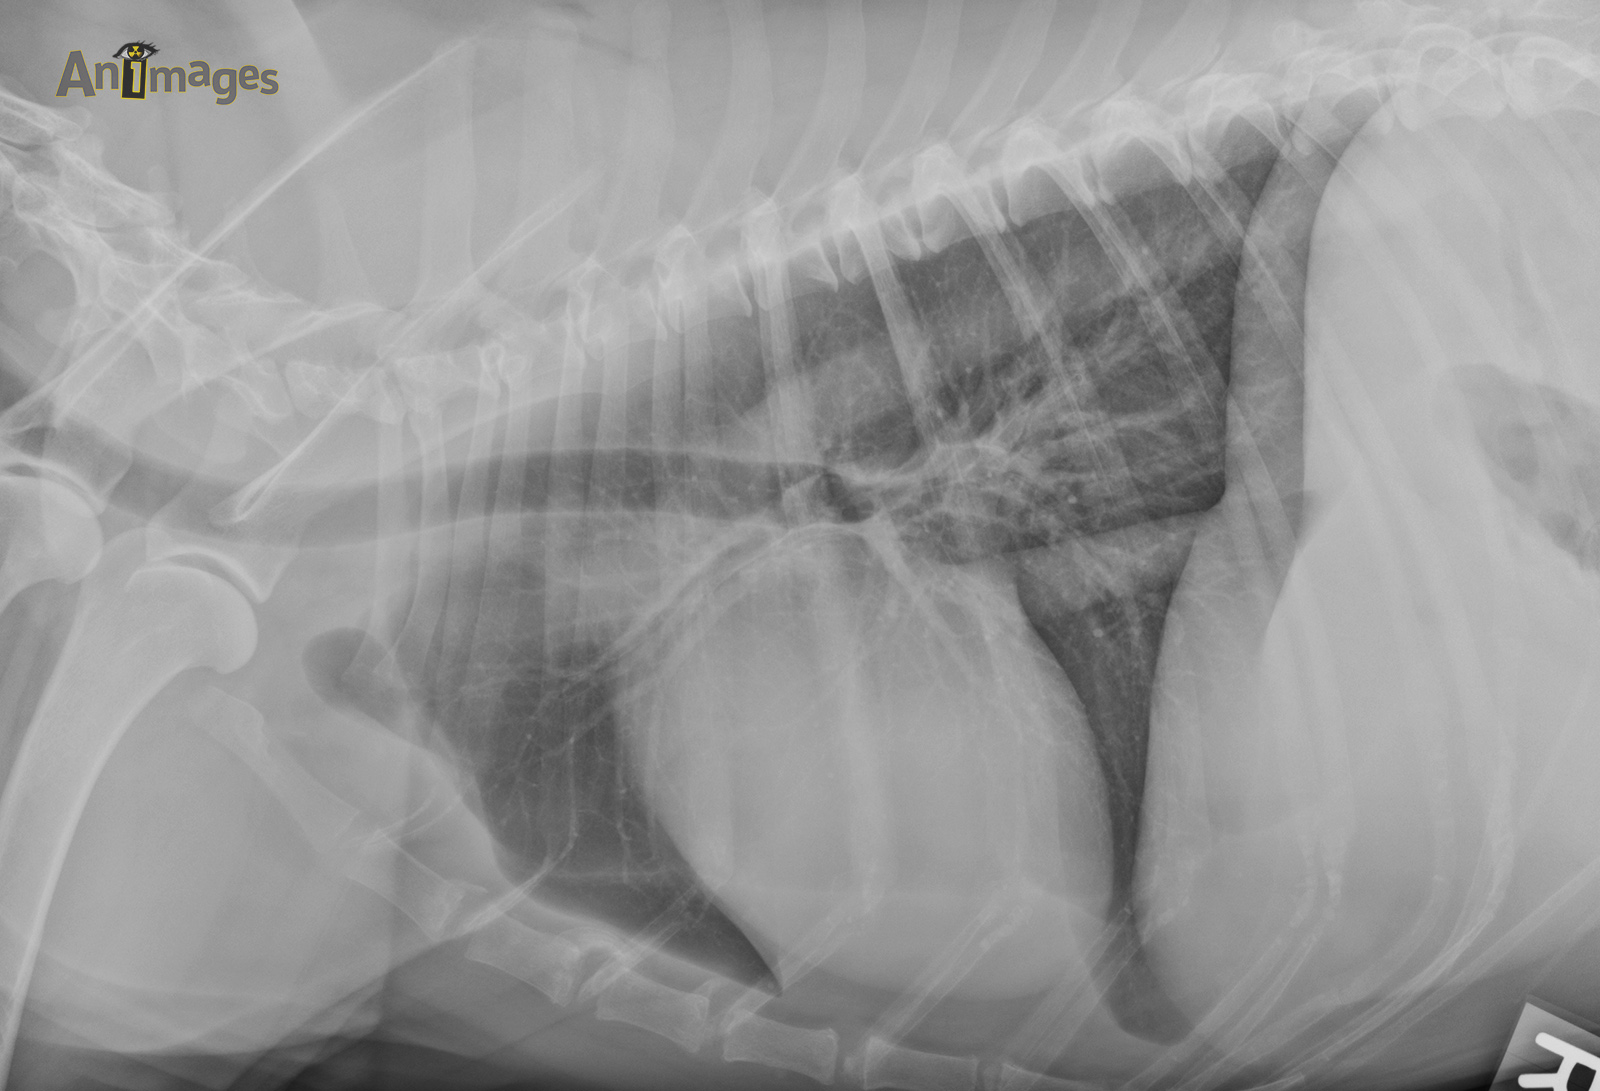

Latérale droite